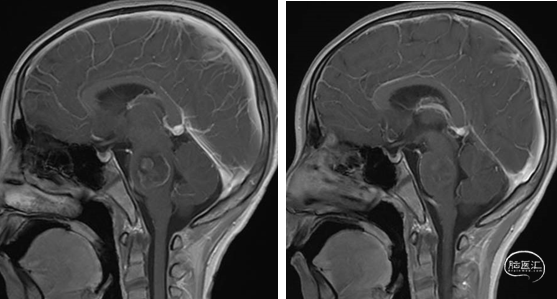

术前MRI

2023年9月13日 MRI T2

2023年9月13日 MRI+C

术后MRI